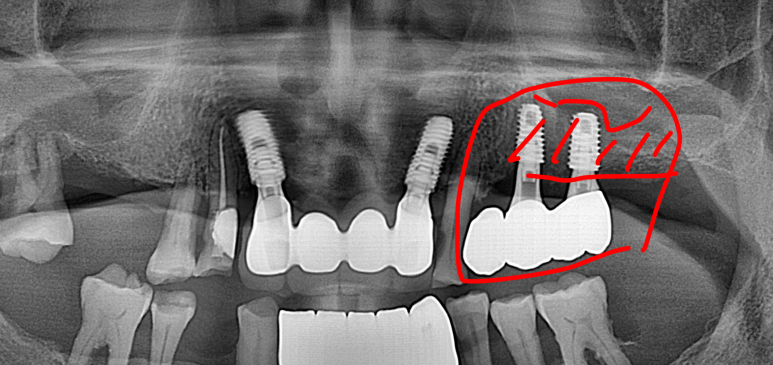

2026년 3월 5일에 촬영된 최종 방사선 사진입니다.

첫 내원일로부터 약 6개월간의 치료 과정이 안정적으로 마무리되었습니다.

하악 전치부에는 임플란트를 지지대로 삼아 브릿지 형태의 보철물이 체결되었고, 뼈가 부족했던 좌측 상악 어금니 부위 역시 상악동 거상술을 통해 튼튼하게 보철물이 완성되었습니다.

방사선 사진에서 확인할 수 있듯, 좌측 상악 어금니 부위는 치아가 빠진 지 오래되어 잔존 치조골(잇몸뼈)이 매우 얇아진 상태였습니다. 임플란트를 단단하게 고정할 뼈가 부족했기 때문에, 위턱뼈 속의 빈 공간인 상악동 막을 조심스럽게 들어 올리고 그 공간에 뼈를 채워 넣는 '상악동 거상술'을 시행했습니다.